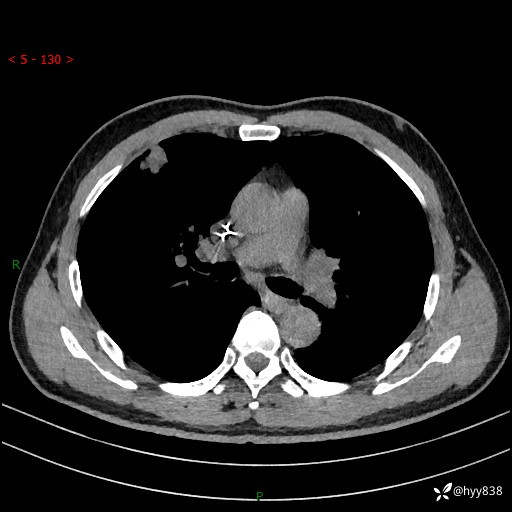

现病史:者10余天前因胸闷就诊于我院心血管内科,行胸部CT提示右肺上叶结节(24mm×16mm),考虑肿瘤性病变可能。无畏寒、发热、盗汗,无咳嗽咳痰,无咯血,无胸痛,无呼吸困难等不适,未予特殊处理。今为求进一步诊治,前来我院就诊,门诊以“肺结节待查”收住入院。 患者自起病来精神、食欲、睡眠尚可,体力下降,体重无明显变化。

胸部CT平扫+增强